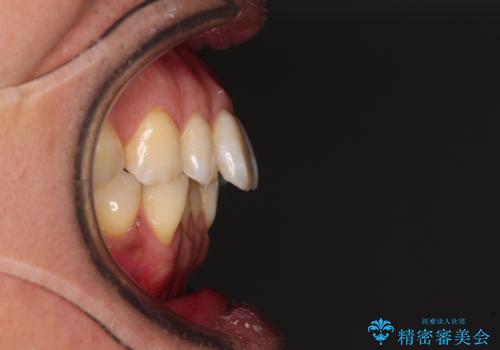

- 口元の突出感を気にして来院された患者様です。

強い咬合力と上顎前歯の傾斜により前歯が突出し、唇が閉じにくい状況であったため、上下左右の第一小臼歯4本を抜歯し、ワイヤー装置にて矯正治療を行うこととしました。